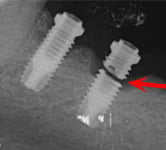

Fractura del implante

La fractura del implante es una ruptura del cuerpo del implante dental, generalmente debido a fuerzas excesivas o defectos en el material.

Los pacientes pueden notar dolor, movilidad del implante y, a veces, una sensación de fragmento suelto en la boca.

El tratamiento incluye la extracción del implante fracturado y la colocación de uno nuevo.